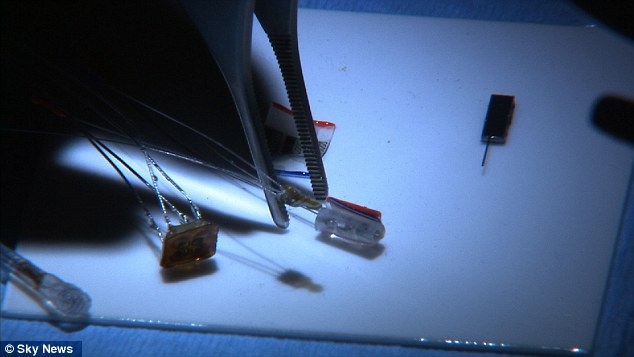

Implant that eases agony of arthritis by zapping a nerve

A tiny disc planted under the skin could offer a revolutionary rheumatoid arthritis treatment and reduce crippling joint pain.

Tiny disc planted under the skin changes signals from body's nervous system to reduce inflammation.

The device, the size of a 50p coin, modifies signals from the body’s nervous system to reduce inflammation caused by the auto-immune disease.

SetPoint Medical is dedicated to treating patients with debilitating inflammatory diseases, such as Crohn's Disease and rheumatoid arthritis, using proprietary implantable neuromodulation devices.

The scientific platform is based on the Inflammatory Reflex—the natural mechanism by which the central nervous system regulates the immune system. This mechanism was discovered by SetPoint co-founder Kevin Tracey and published in Nature in May 2000. Since then, the Inflammatory Reflex has been characterized in more than 100 peer reviewed papers in leading scientific journals. Anti-inflammatory potency comparable to leading drugs has been demonstrated in multiple animal models. The company is currently conducting human trials in rheumatoid arthritis at four European centers.